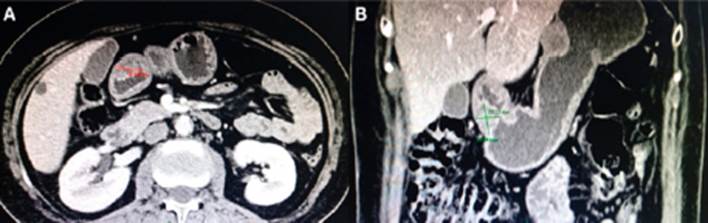

Presentamos el caso clínico de una paciente mujer de 57 años de edad quien consulta por epigastralgia y sensación de llenura precoz, en el examen endoscópico (Figura 1). Presentó doble lesión submucosa en cuerpo en cara anterior de 25 a 30 mm, y otra en antro, a nivel de curvatura mayor tercio medio de 15 x 18 mm. Ambas sospechosas de leiomiomas. Las imágenes de TAC abdominal muestran: dos formaciones expansivas localizadas a nivel de cuerpo, en la cara anterior y antro gástrico, que captan ligeramente contraste de 35,4 x 24 x 23,18 mm (Figura 2) y 24,94 x 20,13 x 18 mm (Figura 3), cuyas características son compatibles con: a. Leiomioma, b. Tumor de GIST.

Figura 3 A y B. Se aprecia lesión en el antro gástrico con cierta captación a la sustancia de contraste, de bordes bien definidos, mide 24.94 mm de diámetro cráneo-caudal x 20.13 mm de diámetro ántero-posterior x 18mm de diámetro transversal.